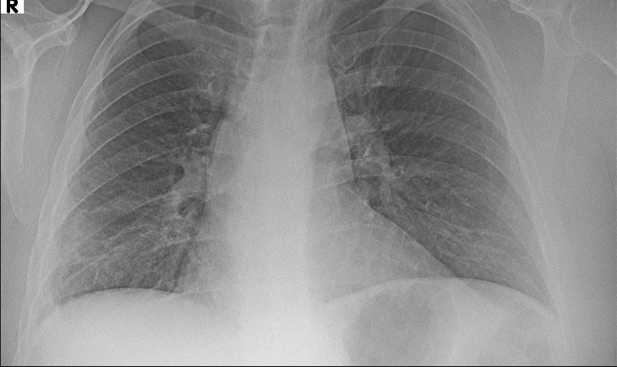

Örnek Röntgen Görüntüsü